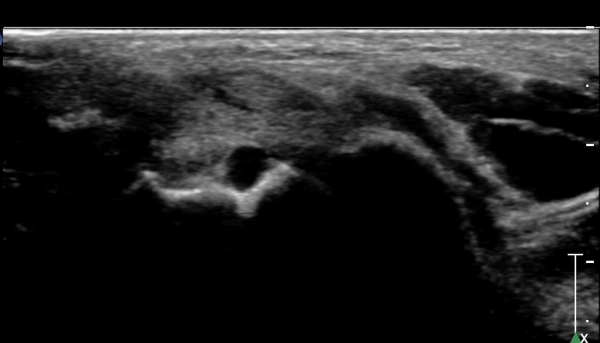

ÇϺΠ½ÅÀü ¶ì(inferior extensor retinaculum) ÀÇ frondiform Àδë Á¾´Ü¸é°Ë»ç¿¡¼­

frondiformÀÎ´ë ½ÉºÎ°¡Áö ÁÖº¯ ¼ö¾×Àú·ù°¡ °üÂûµÇ°í Á·±Ùµ¿ °æºÎÀδ밡 ³Ê¹« ¶Ñ·ÇÈ÷

°üÂûµÈ´Ù(»çÁø 5, 6, 7).

frondiformÀδëÀÇ Àú¿¡ÄÚ ºÎÁ¾°ú °Å°ñÇÏ °üÀý °£°ÝÀÌ ¹ú¾îÁ® ÀÖ´Ù(»çÁø 8, 9).